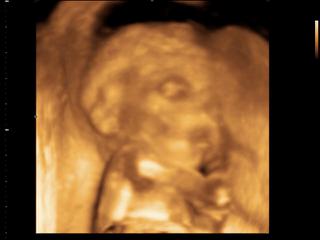

Pozerám, že tu sa už vedia pohlavia a riešia pohyby 😉 Ja môžem zatiaľ riešiť akurát len tie pohyby, ale 7.6. sa to snáď zmení a malé sa nám ukáže v plnej paráde a budeme konečne vedieť, čo čakáme 😀 Prípadne hneď 16.6. sa mi podarilo sa objednať na 3Dcko, tak sa tešííím 😎

No ja som bola dnes tiež na tom morfologickom ultrazvuku a vyzerá to tak, že sme zdravučkí, všetky miery boli tak akurát. Chceli sme aj vedieť, čo to bude, lebo na minulej poradni nám bábo nechcelo ukázať čo má medzi nozičkami. No a teraz to bolo presne to isté. Naše malé malo nožičky prekrížené na brušku a ani za svet nám nechcelo ukázať čo to tam má. Nakoniec sa otočilo chrbátikom a bolo po paráde :D :D :D Tak doktorka kukala aspoň zospodu a keďže stále nebolo vajíčka, povedala že to bude asi dievčatko, lebo mu tam nič nevisí :D :D :D No a najhoršie je, že do ďalšej poradne ideme až 30.6 to bude aj ten glukózový test. To je celý mesiac katastrofaaaa, nevydržím to. 😀 😀